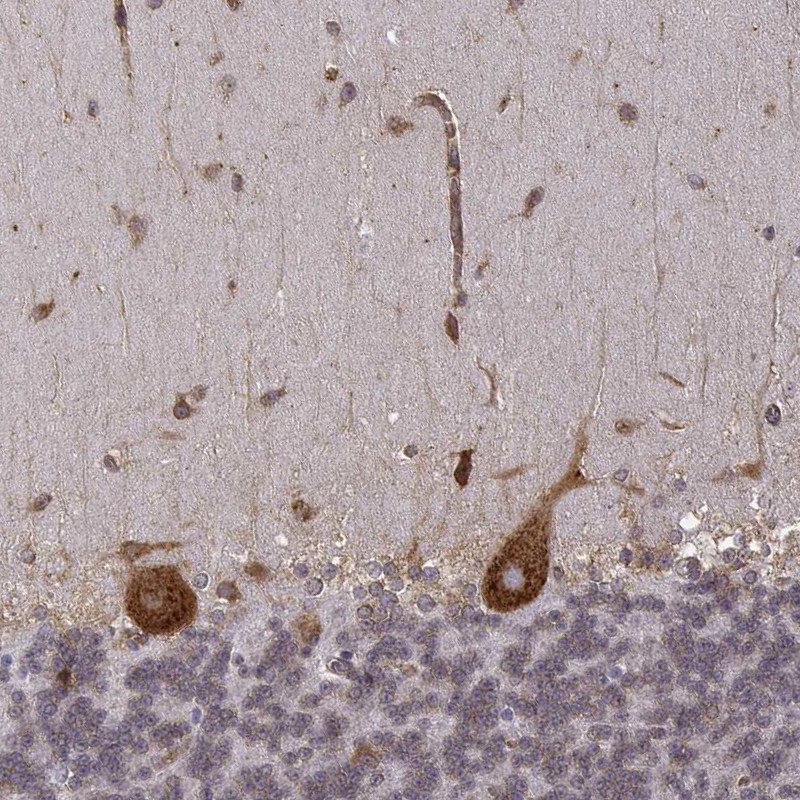

Immunohistochemical staining of human cerebellum shows strong cytoplasmic positivity in purkinje cells.